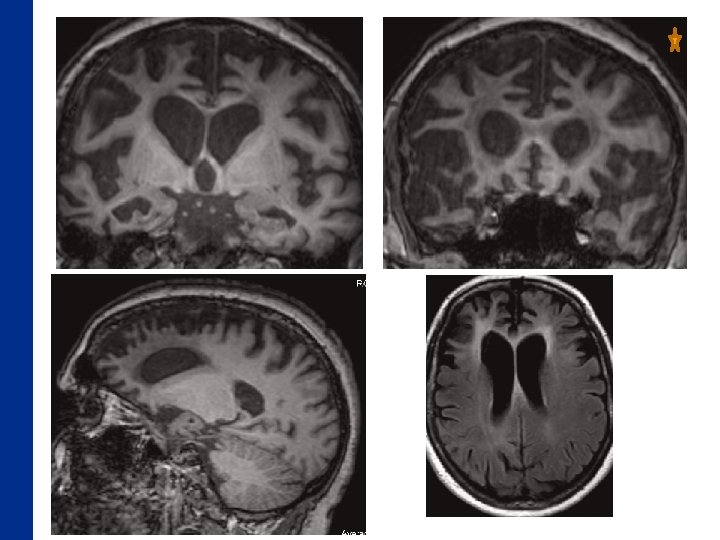

Que vous évoque cette IRM ? A) une MA B) une DFT C) un AVC bifrontal

La Démence Frontotemporale • 3 eme cause de démence neurodégénérative • Regroupe différents syndromes: – Comportemental – Langage Rabinovici Am J Alzheimers Dis Other Demen. 20

La Démence Frontotemporale • 3 eme cause de démence neurodégénérative Imagerie : Regroupe différents syndromes: – • Atrophie prédomine dans les régions antérieures du lobe – Comportemental frontal et du lobe temporal, – Langage épargnant relativement les régions temporales médiales. – Atrophie bilatérale des hippocampes et du cortex entorhinal qui prédomine sur la partie antérieure. – Hypersignal Flair des régions antérieures fréquent. Rabinovici Am J Alzheimers Dis Other Demen. 20

DFT

Atrophie fronto temporale Anomalie de signal des régions frontales Diagnostic évoqué : dégénerescence fronto temporale, début sous forme d’une aphasie progressive